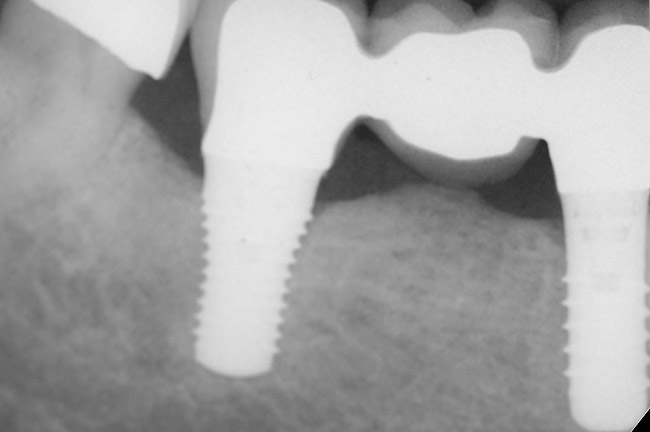

Figure 7  Condition of the teeth seen in Figure 6, approximately 5 years after restoration. Note the extensive furcation involvement of tooth No. 31 and its residual periapical radiolucency.

Figure 7

Figure 8  Same case as in Figure 7 showing teeth Nos. 28 and 29. Note that tooth No. 28 was included into the four-unit restoration, and the small radiolucency on the distal tooth No. 29, which was associated with a root fracture.

Figure 8